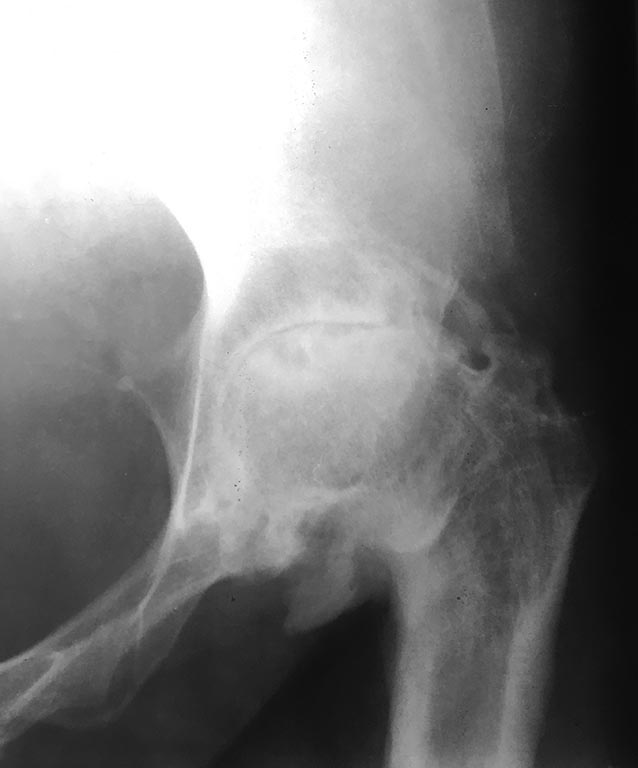

Пациентка 38 лет жалобы на ограничение движений, боль в области тазобедренного сустава, укорочение конечности, хромоту.

В возрасте 6 лет открытое вправление пропущенного врожденного вывиха левой бедренной кости, осложнившееся кокситом.

На данный момент: Сгибательная приводящая установка в суставе, движения отсутствуют.

Обращает на себя внимание втянутый рубец плотно спаянный непосредственно с костью в области большого вертела без подлежащих мягких тканей

«Костный этап» больших вопросов не вызывает, а вот состояние мягких тканей и перспективы оставить протез «под кожей» несколько смущают.